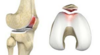

# Knee: ACL Tear Etiology and presentation

Etiology: Tear of ligament, usually because of twisting injury or direct blow to the knee Often because of sport injury – basketball. soccer Presentation: **Pain deep in knee (not always) Instability “Pop” in the knee Immediate swelling/effusion**

# Knee: ACL Tear PE and tests

Physical Exam: Effusion Little to no TTP **+ Lachman + Anterior drawer** “Quadriceps avoidance” – do not want to extend the knee Tests: MRI Lachman + Anterior drawer test +

# Knee: ACL Tear Tx

Treatment: Almost always need surgical repair (unless older and inactive) - Femoral/tibial tunnel, graft fixation - Bone-Patella-Bone autograft*, quad tendon/ham autograft, allograft - Repair associated damaged structures (meniscus/MCL) ACL brace during recovery controversial Physical therapy after surgery Pearls: Often associated with MCL or medial meniscus injury (50%)